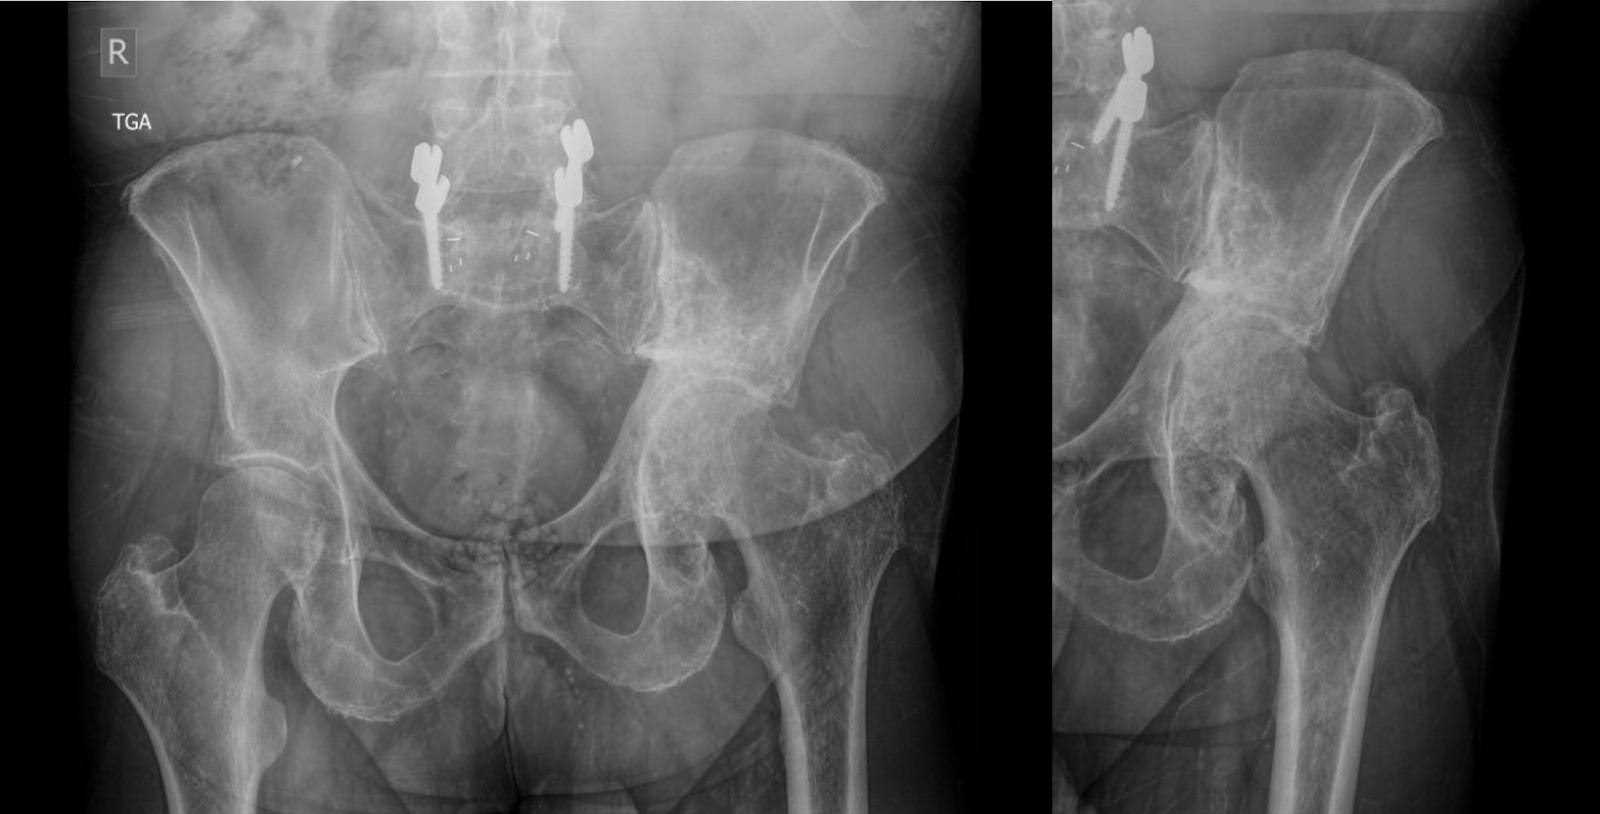

Subsequent X-ray imaging, conducted three months preoperatively, revealed no substantive change in the appearance of mixed sclerotic and lytic lesions within the left hemipelvis, in keeping with treated lymphoma. This was accompanied by acetabular remodeling and cranial migration of the proximal femur, with degenerative changes in the left hip joint (Figure 1). Computed tomography (CT) findings aligned with those on X-ray, affirming the observed pathology (Figure 2).

Figure 1. Anteroposterior (AP) X-rays of the pelvis three months prior to surgery. Primarily sclerotic lesion of the left hemipelvis, consistent with treated lymphoma. Structural changes of the acetabulum with remodeling and superior migration of the proximal femur.